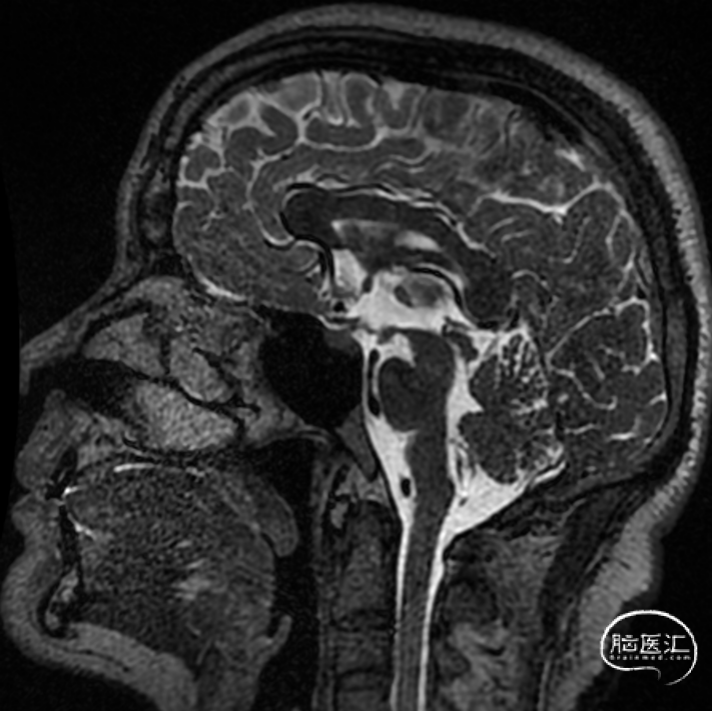

图2:颈髓MRI水成像未见异常。